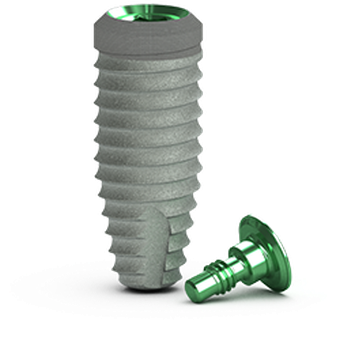

Tapered Internal Tissue Level De BioHorizons®

Características técnicas

- Nivel: Nivel de tejido

- Tipo de conexión: Interna

- Forma de conexión: Hexágono

- Forma del cuello: Ensanchado

- Micro roscas de Cuello: No

- Forma del cuerpo: Ápice cónico

- rosca del cuerpo: Diente de sierra inverso

- Forma del Ápice: Domo

- Agujero del Ápice: Sin agujero

- Ranuras del Ápice: Sí

Tapered Internal Tissue Level es un implante dental estándar producido por BioHorizons. Es un implante nivel de tejido. Su conexión es interna, de forma hexágono con bisel interno. Su cuerpo es ápice cónico con roscas diente de sierra inverso. Su cuello es ensanchado. Su cabeza tiene un bisel. Su ápice es domo, no tiene un agujero, y tiene ranuras. Está disponible en 4 diferentes diámetros y 4 diferentes longitudes. Este modelo de implante es bastante reciente. Requiere un destornillador de forma hexágono. Para más detalles, consulte el catálogo. BioHorizons también ofrece 23 otros modelos de implantes.